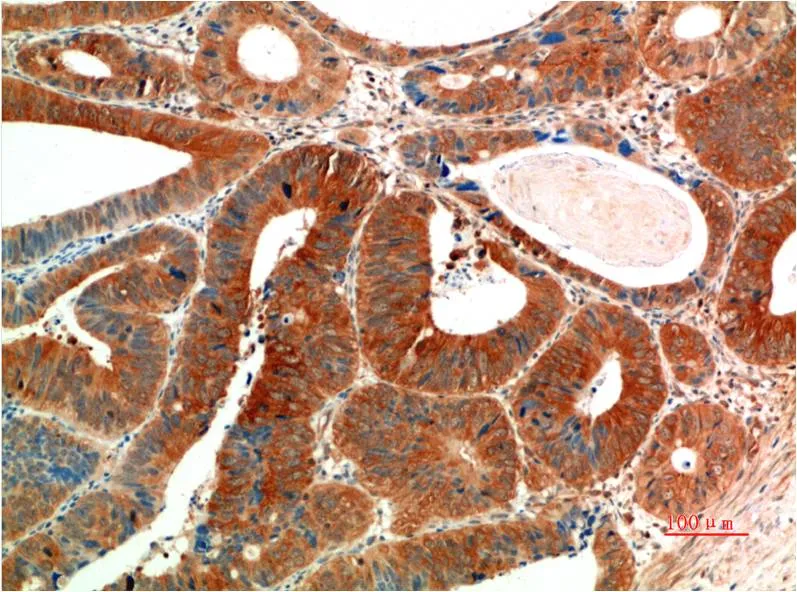

Desmin (4H1) Mouse Monoclonal Antibody

Cat: AMM00779

Size1:50μl Price1:$150

Size2:100μl Price2:$280

Size3:500μl Price3:$1200